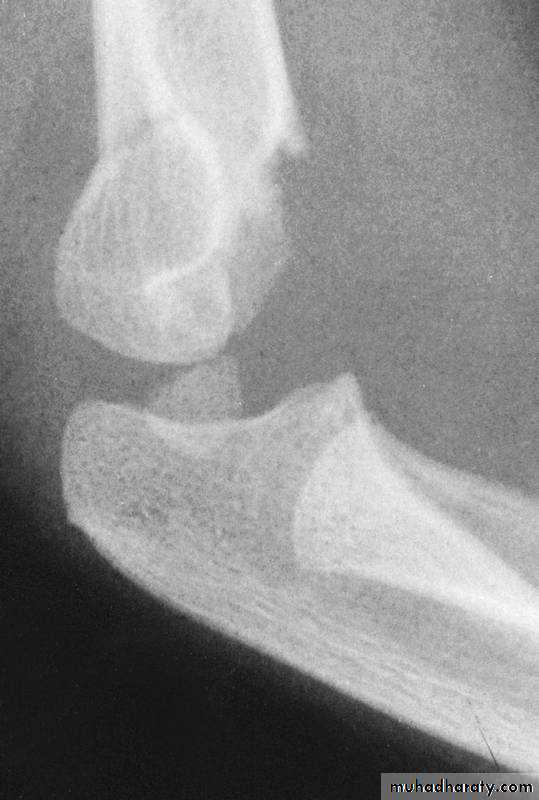

2. The distal fragment is in valgus.

3. The medial spike of the proximal fragment is usually posterior.

How are the extension type supracondylar

humeral fractures further classified?*

Type I

No displacementType II

Incomplete

displacement

Type III

Complete